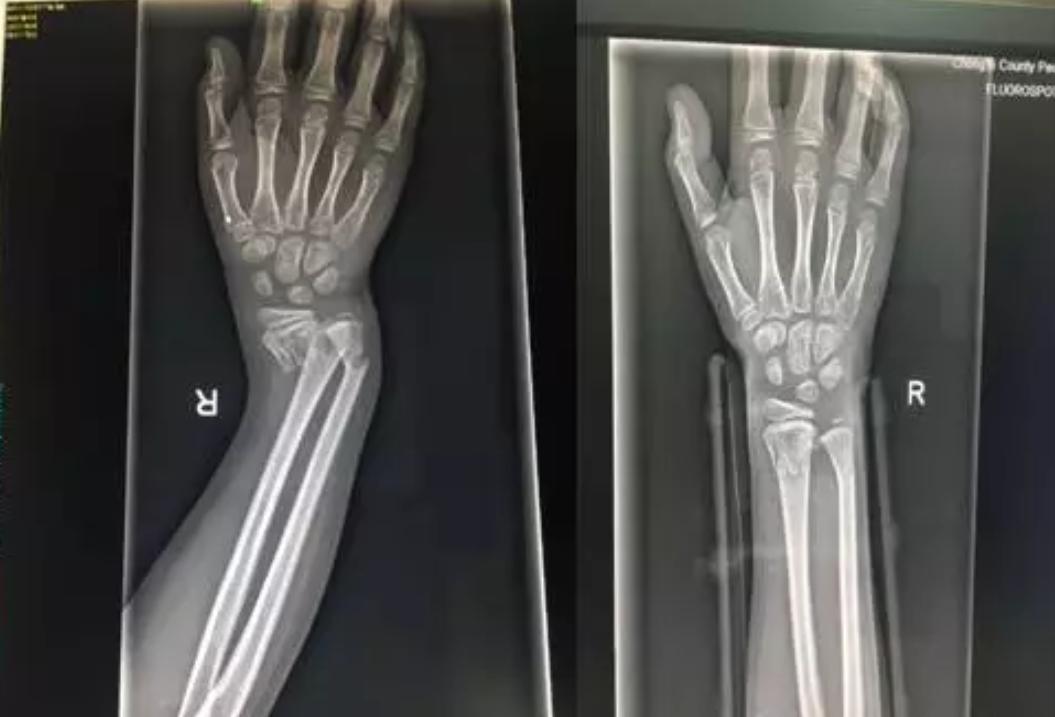

由上图可以看出孩子的右手腕明显的畸形

DR片提示右桡尺骨远端骨折。因为骨折严重错位,孩子疼痛的已经脸色惨白,我们将治疗方式提供给患儿家属,征得同意后实施正骨手法复位。准备好一切所需要的物品,如绷带、夹板、扎带、棉垫、压垫。孩子很坚强,积极配合,吴医生与朱医生默契配合,在场的人都屏住呼吸,希望医生可以一次复位成功,避免孩子再承受更多的痛苦。牵引、复位一气呵成。

在场的人都松了一口气,固定夹板,交待注意事项,复查。让我们看看复查前、后的DR片吧!